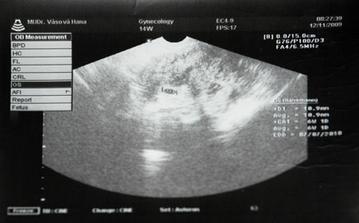

Ako rýchlo rastieme v brušinku 🙂